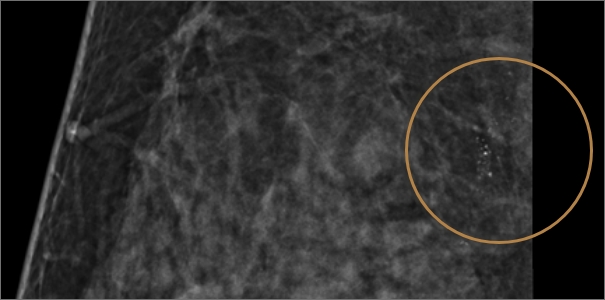

미세석회화

미세석회화란 몸 안에 쌓인 칼슘 성분의 석회질을 뜻합니다.

유방촬영 시 하얀 점으로 보이며 노화, 유선 내 분비물 침착, 염증 등으로 생길 수 있습니다.

대부분의 경우 양성 석회화로 인체에 무해하지만, 유방암으로 인해 생기는 악성 석회화가 의심될 시

조기 발견과 치료를 위해 반드시 조직검사를 통한 악성 여부 확인이 필요합니다.

치밀유방 여성, 우측 미세석회 발견

진공흡인 보조장치(맘모톰) 조직 채취 후

암 진단 판정